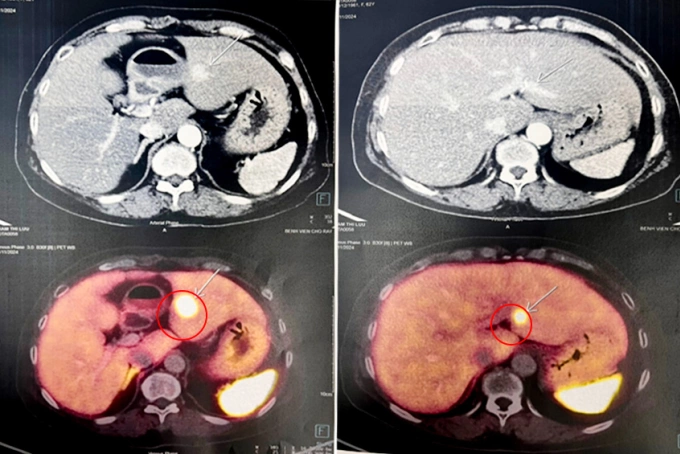

Ảnh CT ghi nhận các khối u gan, tụy (ảnh đen trắng) và chụp DSA là u tuyến nội tiết (màu vàng). Ảnh: Bệnh viện Đa khoa Tâm Anh

Ổn định sau phẫu thuật tuyến giáp, bà Long được điều trị các khối u gan và tụy còn lại. Khối u gan được đốt bằng sóng cao tần. Khối u ở thân tụy có kích thước dưới 2 cm, nằm ở vị trí không thuận lợi, không thể đốt sóng cao tần mà chỉ theo dõi và điều trị nội khoa.